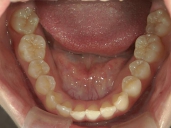

矯正歯科 治療後

矯正歯科 治療後 下顎